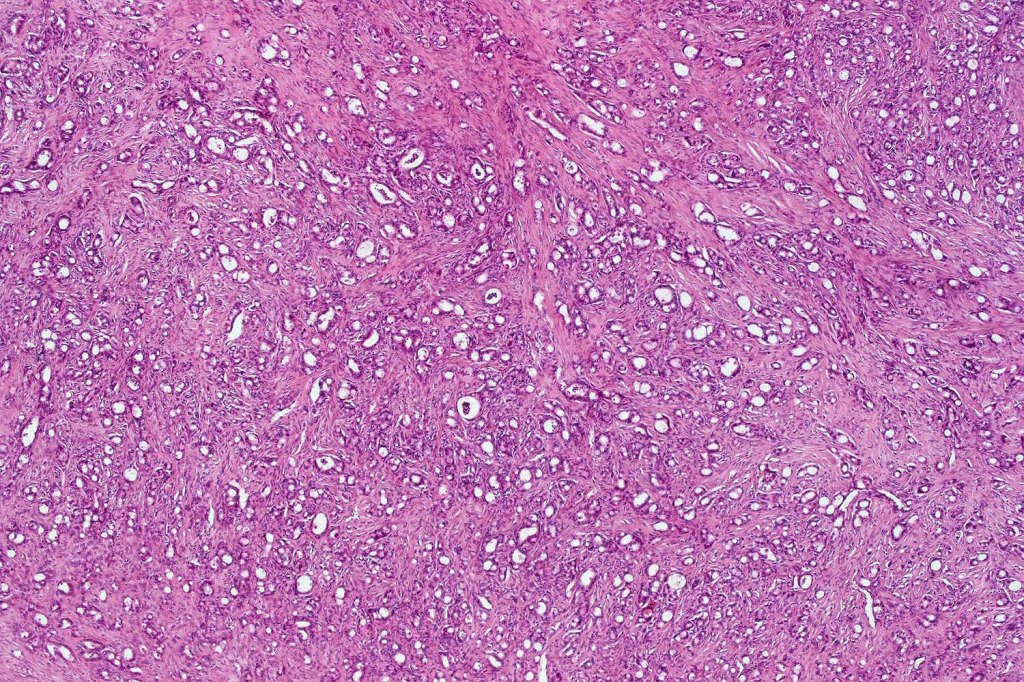

Histological features

Dermal tumor +/- subcutaneous fat

•Nests & cords of epithelial cells showing ductal differentiation/intracytoplasmic lumina embedded in a dense fibrous stroma

•Eosinophilic cytoplasm & irregular vesicular nuclei with small nucleoli

•Variable pleomorphism & mitoses

•Perineural infiltration & lymphovascular invasion commonly present